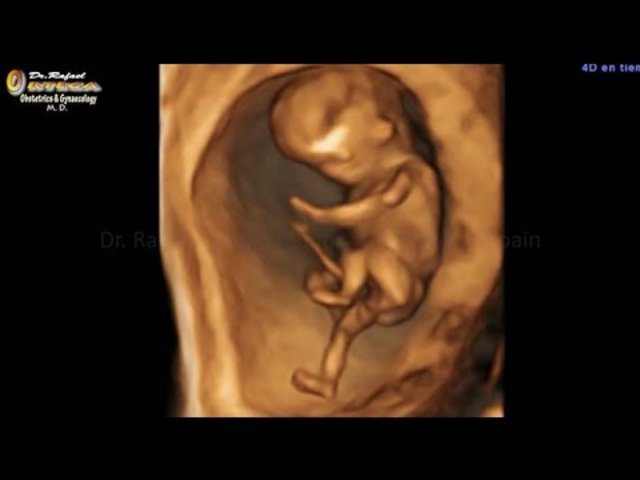

• SEMANA 7

Se observa hipo, movimiento de las piernas.

El corazón de 4 cámaras esta prácticamente completo, y late 167 veces por minuto.

Se registra actividad eléctrica cardíaca.

A las 7 semanas y media se observa la retina pigmentada y los parpados.

Los dedos de las manos ya están separados y los dedos de los pies estan unidos solo por las bases